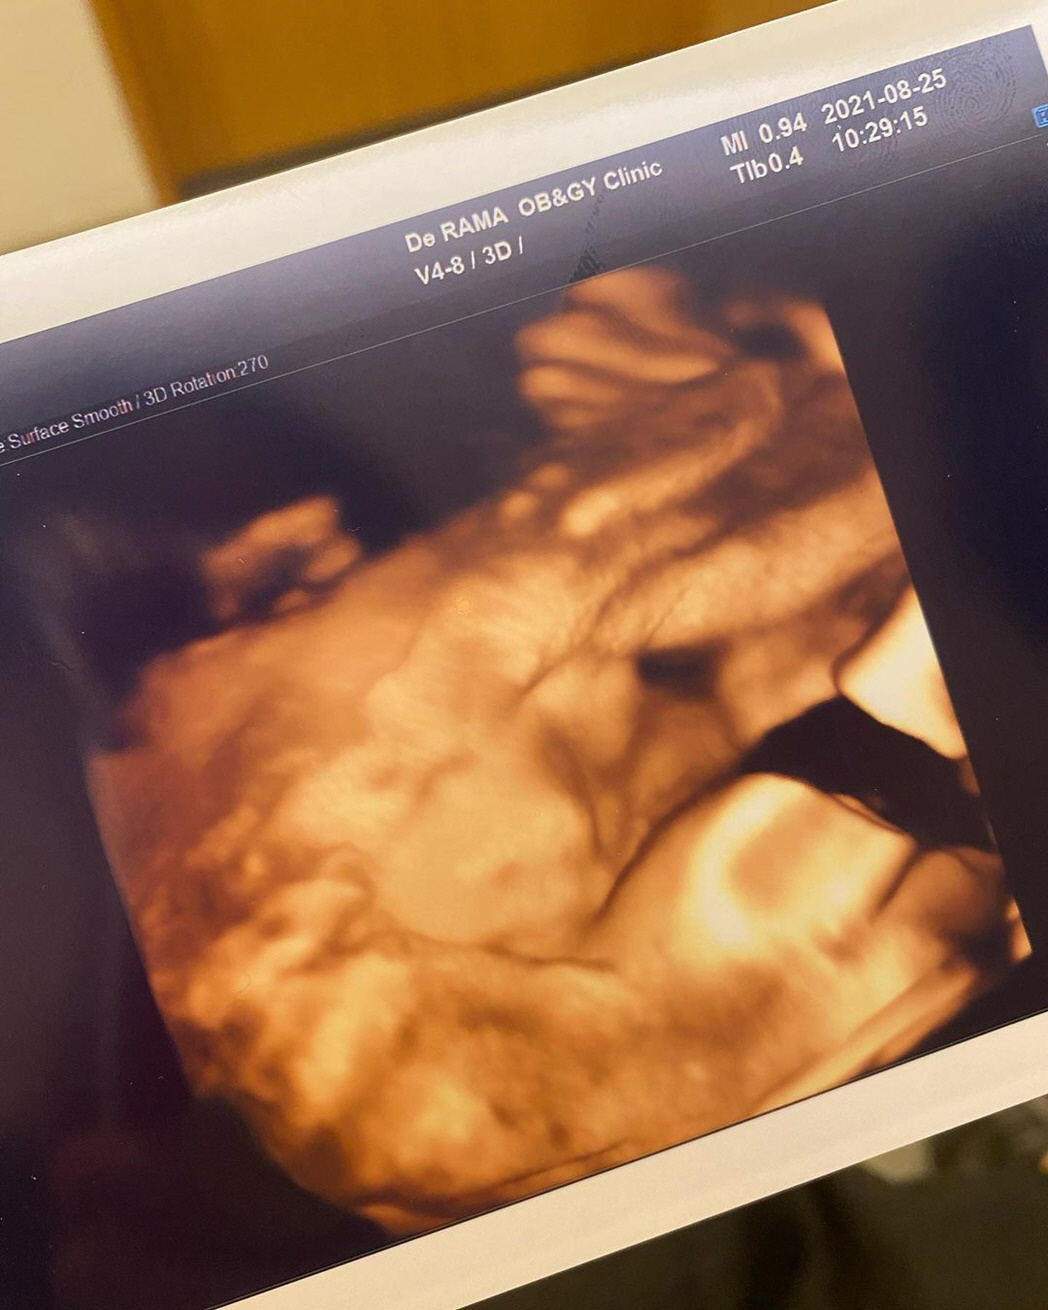

앞서 정아는 일주일 전에도 SNS를 통해 초음파 사진을 공개하며 "몸무게1.7kg 아주 정상이예요^^ 조금만 더 있다가 만나자 내 사랑 제니야"라고 전하기도 했다.